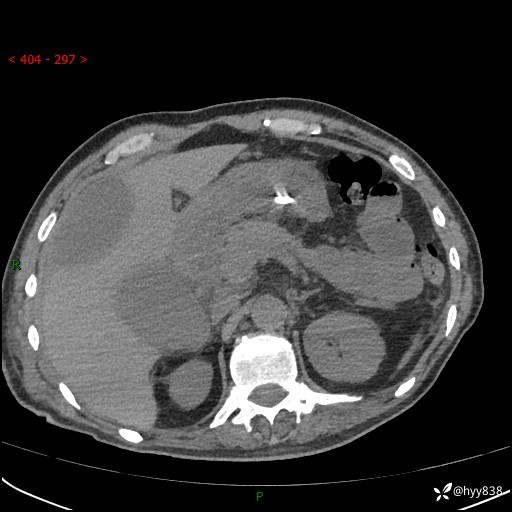

腹部CT平扫

增强